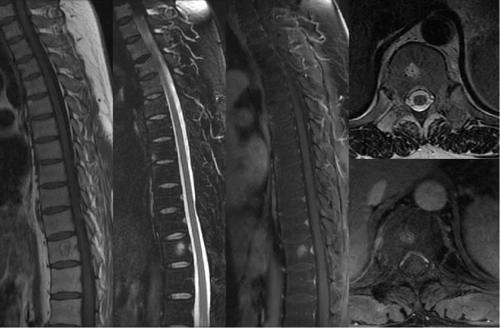

Case9:F,11y。

文章插图